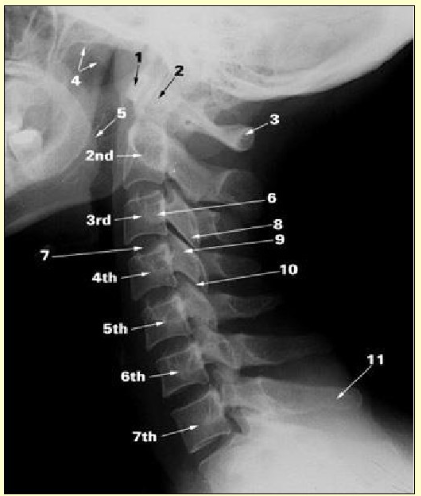

Label this image

anterior arch of the atlas

dens of axis

posterior arch of atlas

soft palate

root of tongue

transverse process

intervertebral disc

inferior articular process

superior articular process

facet joint

spinous process of C7